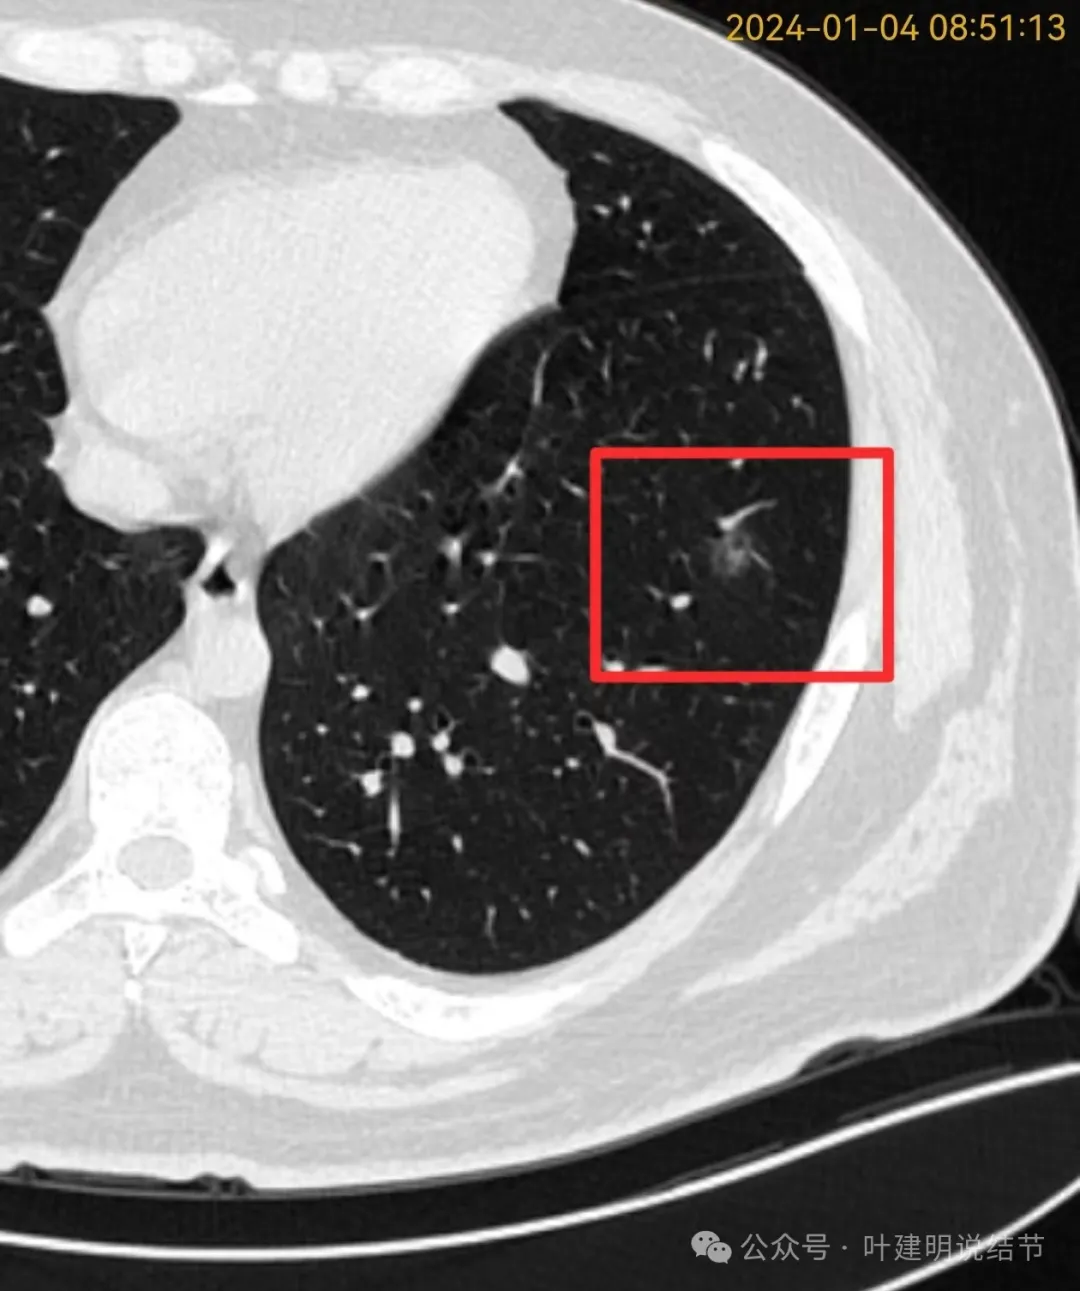

我们先来看2024年1月份的影像最明显的层面:

病灶磨玻璃密度,不太纯,轮廓清楚,灶内有小空泡征,整体轮廓与边界清楚。

血管贴边,病灶与血管间间隙不太明显,灶内密度稍显不均。